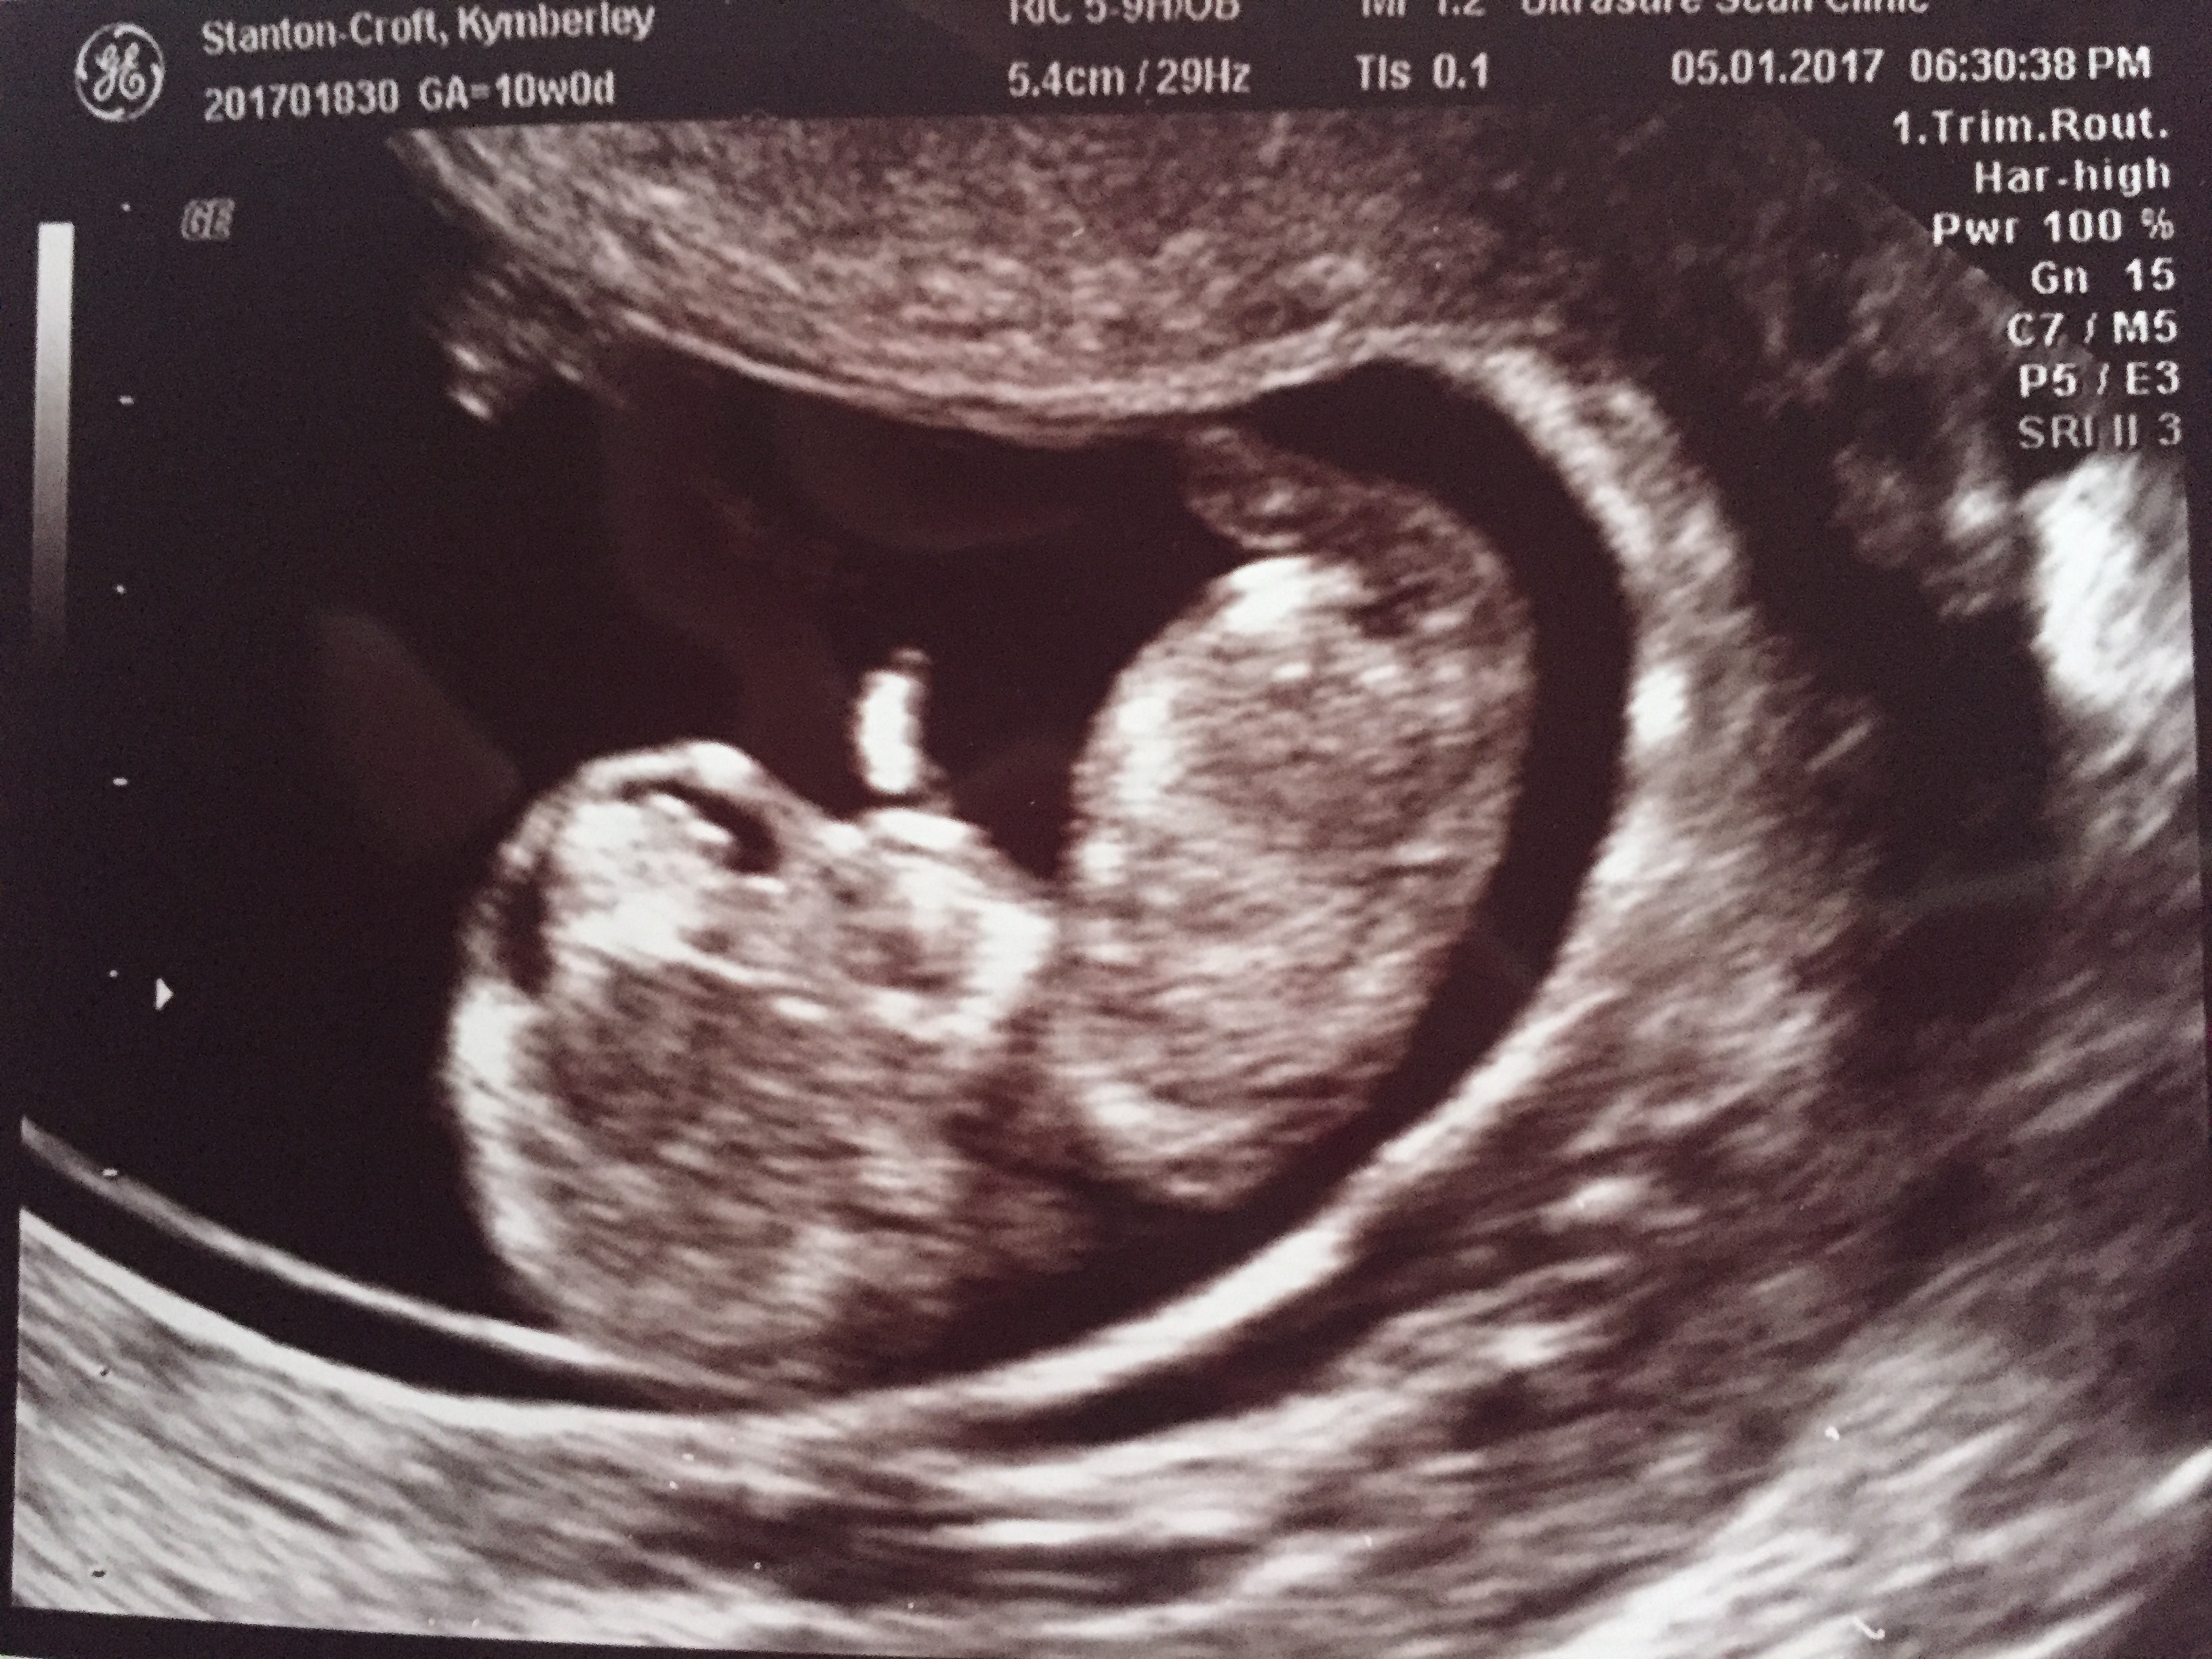

12 weeksAttachment 35788